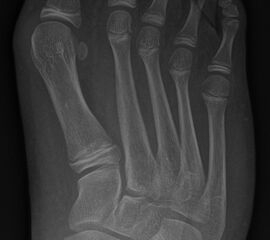

Abb. 2 a-c: offene Wachstumsfugen MT I Basis und Zehen (a), teilweise geöffnete Wachstumsfugen (b) und geschlossene Wachstumsfugen (c).

In der Regel bestehen aktive Wachstumsfugen bei Mädchen bis zum 12. und bei Jungen bis zum 14. Lebensjahr, mit Abweichungen von einem Jahr nach unten und nach oben. Präzise Informationen unter anderem darüber gibt das präoperative Röntgenbild (Abb. 2).